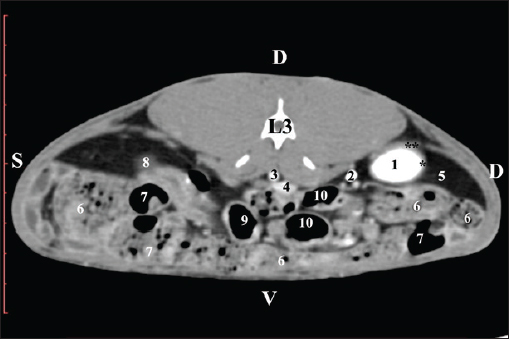

The transverse pre-contrast examination of the regio abdominis media at the L3 level (through the cranial part of the vertebra) revealed the left kidney’s extremitas cranialis as an oval soft tissue with normoattenuated soft tissue characteristics. Ventrally, the kidney was adjacent to the duodenal pars ascendens, ileum, colon ascendens, and colon descendens. Hypoattenuated abdominal adipose collections were observed around it (Figs. 8 and 9).

Fig. 8. Pre-contrast computed tomography (CT) anatomical scan of the regio-abdominis media at the cranial L3 edge level. (1) Ren sinister; (2) adipose collections; (3) cecum; (4) colon ascendens; (5) jejunum; (6) pars ascendens of the duodenum; (7) colon descendens; (8) colon transversum; (9) colon descendens.

Fig. 9. Pre-contrast computed tomography (CT) anatomical scan of the regio-abdominis media at the caudal L3 edge level. (1) Ren dexter; (2) adipose collections; (3) cecum; (4) colon ascendens; (5) jejunum; (6) pars ascendens of the duodenum; (7) colon descendens.